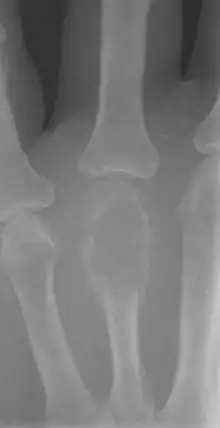

X-ray of a giant cell bone tumor in the head of the 4th metacarpal of the left hand.